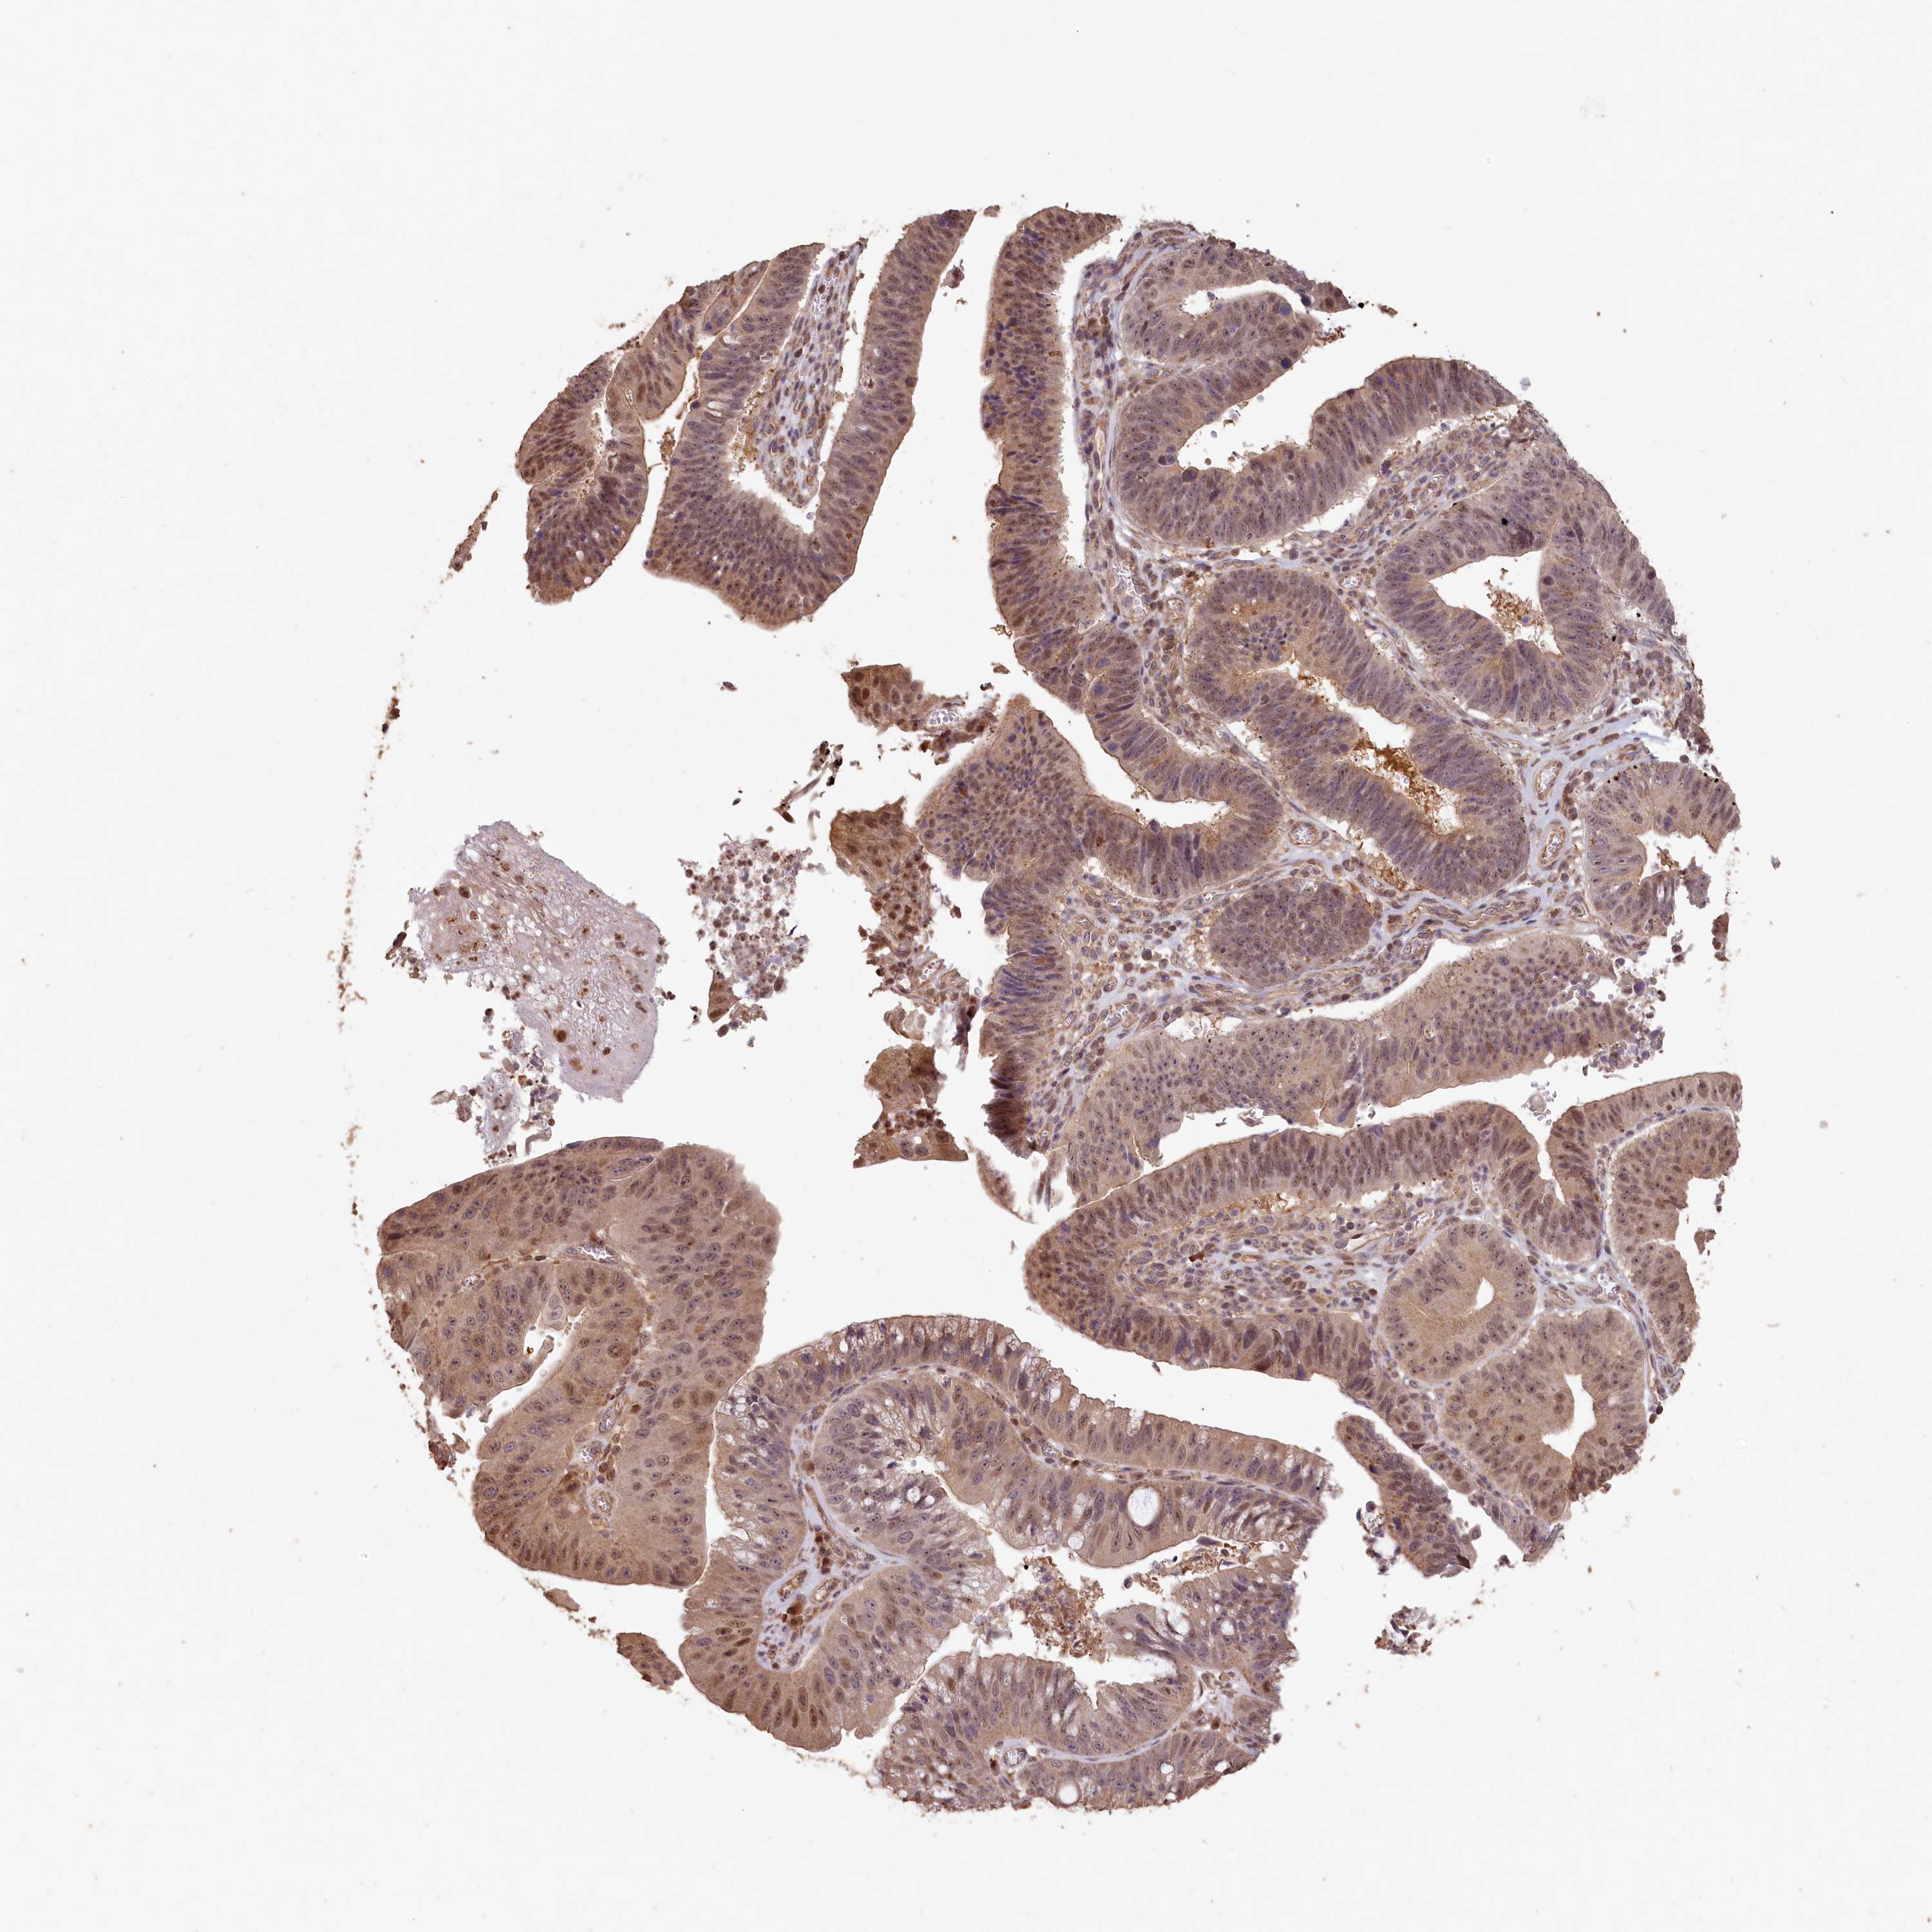

STOMACH CANCER - Protein expressioni

A mouse-over function shows sample information and annotation data. Click on an image to view it in a full screen mode. Samples can be filtered based on level of antibody staining by selecting one or several of the following categories: high, medium, low and not detected. The assay and annotation is described here.

Antibody stainingi

Antibody staining in the annotated cell types in the current human tissue is reported as not detected, low, medium, or high, based on conventional immunohistochemistry profiling in selected tissues. This score is based on the combination of the staining intensity and fraction of stained cells.

Each image is clickable and will lead to virtual microscopy that enables deeper exploration of all samples and also displays staining intensity scores, fraction scores and subcellular localization as well as patient and tissue information for each sample.

Antibody HPA038568

Staining

High

Medium

Low

Not detected

Intensity

Strong

Moderate

Weak

Negative

Quantity

>75%

75%-25%

<25%

None

Location

Nuclear

Cytoplasmic/membranous

Cytoplasmic/membranous,nuclear

Adenocarcinoma, NOS